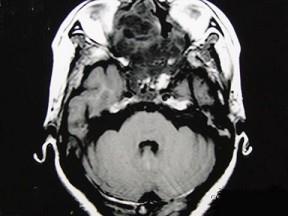

问题 女性,41岁,鼻腔流脓涕3年,鼻部面部肿胀1年,近来加重,MRI检查如图,请选择最可能诊断 ( )

选项 A、鼻咽癌 B、鼻腔血管瘤 C、鼻腔内出血 D、鼻腔软骨瘤 E、鼻腔内囊肿

答案 D